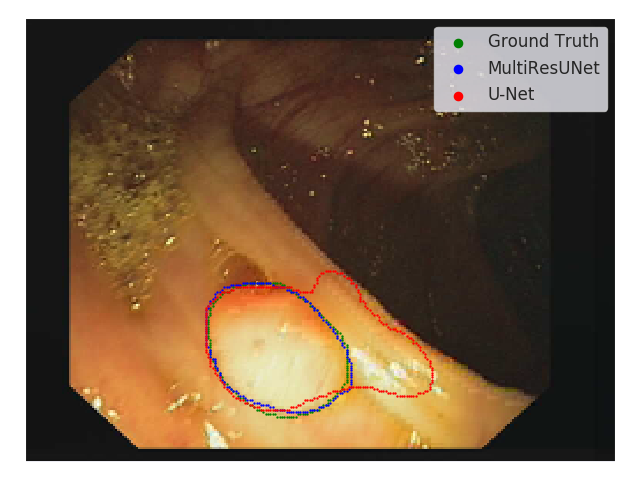

Being the current state of the art model for medical image segmentation, U-Net has demonstrated quite satisfactory results in our experiments. For instance, in Fig. 7, for a polyp with clearly distinguishable boundary the U-Net model manages to segment it with a high value of Jaccard Index; our proposed model however performs better albeit only slightly.

Refer to caption

Figure 7: Segmenting a polyp with clearly visiable boundary. U-Net manages to segment the polyp with a high level of performance (J.I. = 0.9678). MultiResUNet segments just slightly better (J.I. = 0.9697)

But as we study more and more challenging images, especially with not so much conspicuous boundaries, U-Net seems to be struggling a bit (Fig. 8). The colon polyp images often suffer from the lack of clear boundaries. On such cases, the U-Net model either under-segmented (Fig. 8(a)) or over-segmented (Fig. 8(b)) the polyps. Our proposed MultiResUNet, on the other hand, performed considerably better in both the cases. However, there are some images where both the models faced complications, but in those cases MultiResUNet’s performance was superior(Fig. 8(c)). Dermoscopic images have comparatively clearer defined boundaries; still in those cases MultiResUNet delineats the boundaries better (Fig. 8(d)). Same was observed for other types of images. We hypothesize that the use of multiple filter sizes allows MultiResUNet to perform better pixel perfect segmentation.

Figure 8: Segmenting images with vague boundaries. This issue is more prominent for Colon Endoscopy images. U-Net seems to either under-segment (8(a)), or over-segment (8(b)) the polyps. MultiResUNet manages to segment polyps of such situation much better. However, some images are too problematic even for MultiResUNet, but in those cases as well it performs beter than U-Net (8(c)). Even in dermoscopy images, where there exists a clear boundary, U-Net sometimes produced some irregularities along the boundaries, but MultiResUNet was much more robust (8(d)).